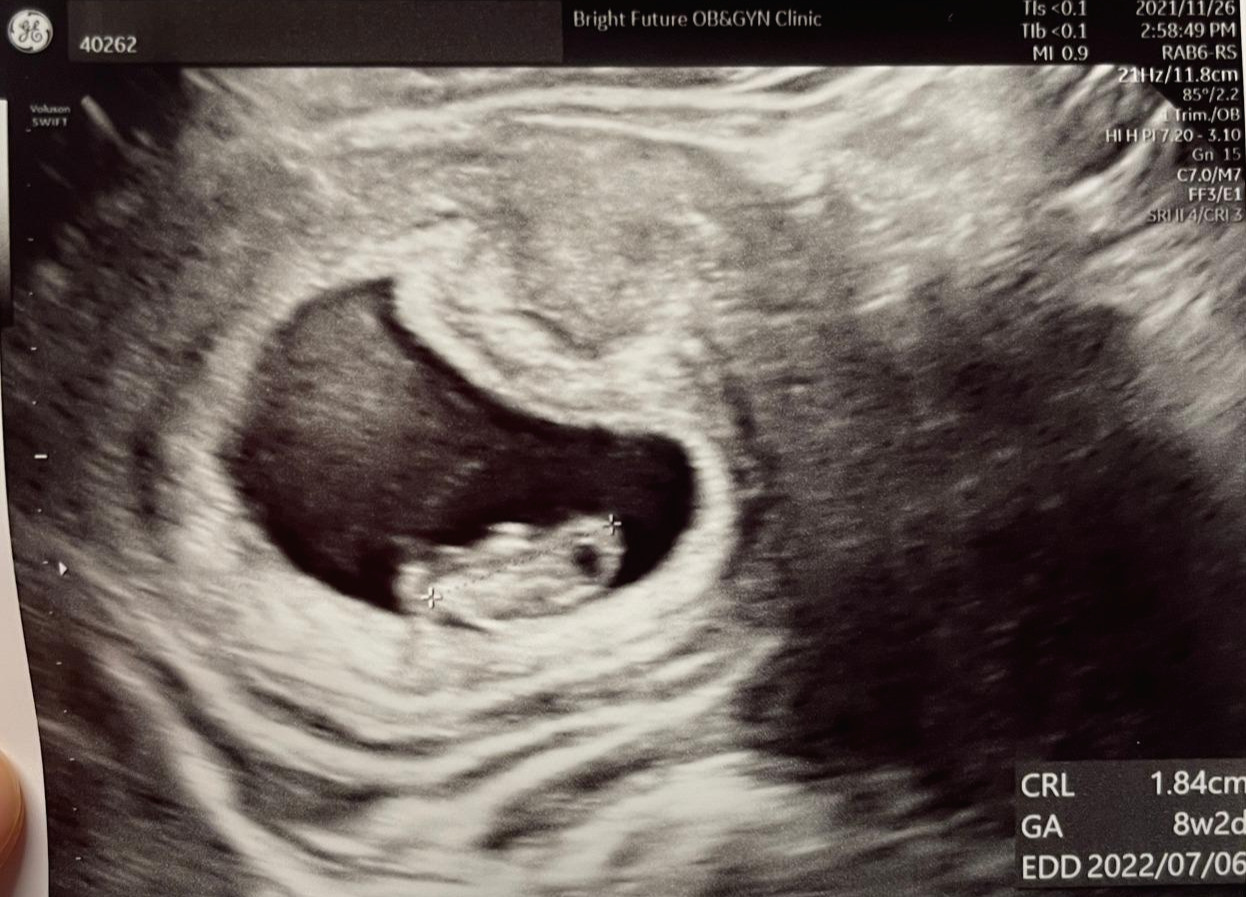

하지만 2주마다 쑥쑥 크는 아기 초음파를 보며, 작게 움직이는 아기의 움직임을 보며 느낀 벅찬 감정은 모든 부정적인 감정을 잊게 해 줬다.

작은 아기집에서 난황과 작은 아기, 손과 발이 생겨서 꼼지락대기까지 성장한 아기의 모습

내 자식이 행복하게 잘 크길 기원하면서 말이다. 아기의 팔다리가 나오는 게 보이자, 집에 돌아가는 길에 단백질이 함유된 요플레와 건강한 샐러드를 사 온 나처럼.

당장 울렁이고 못 먹겠더라도 초음파 속 아기 팔다리가 만들어지고 있는데 건강하게 잘 크도록 지켜주고 싶었기 때문이다. 튼튼하고 무탈하게 잘 크길 바라면서 말이다.